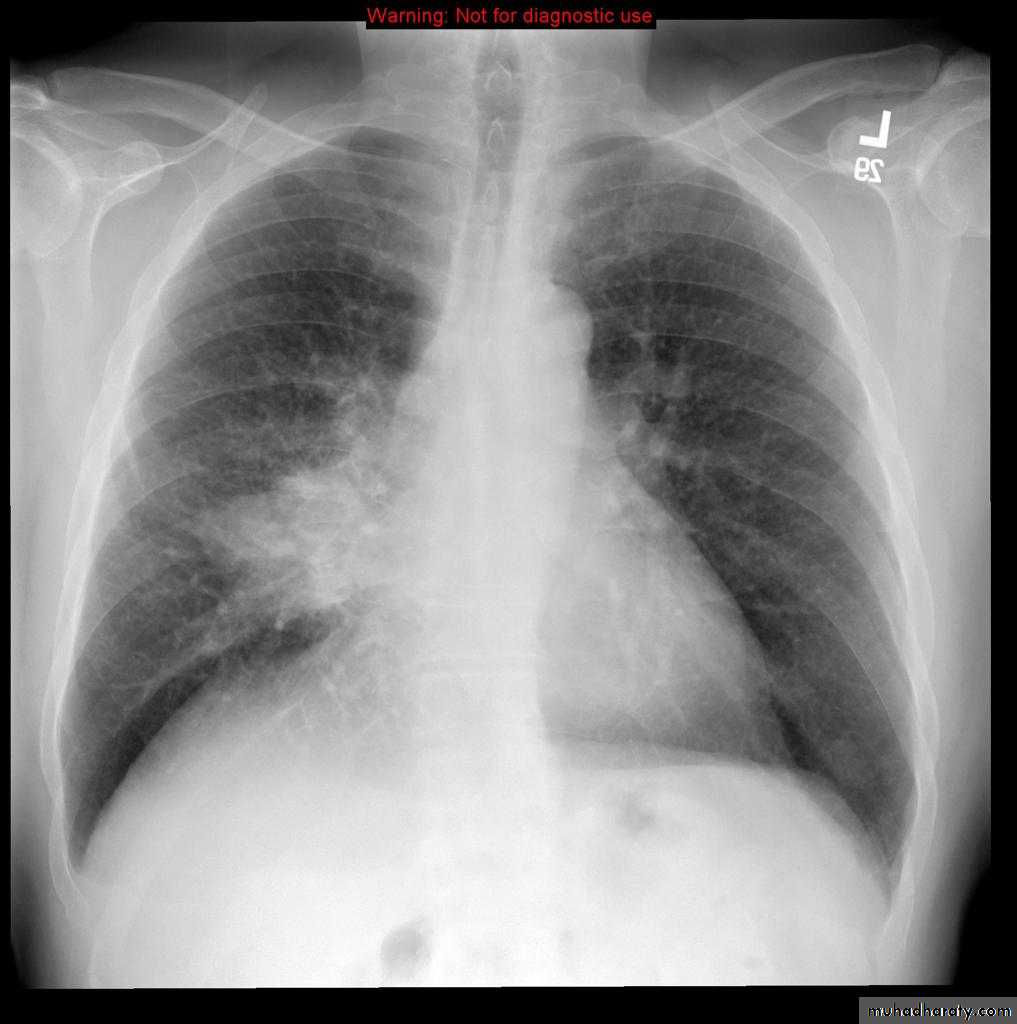

Left lower lobe collapse has distinctive features, and can be readily identified on frontal chest radiographs, provided attention is paid to the normal cardiomediastinal contours. The shadow cast by the heart does however make it harder to see than the right lower lobe collapse

Radiographic features

Left lower lobe collapseis readily identified in a well penetrated film of a patient with normal sized heart, but can be challenging in the typical patient with collapse, namely unwell patients, with portable (AP) often under-penetrated films, often with concomitant cardiomegaly. Features to be observed include :

triangular opacity in the posteromedial aspect of the left lung

edge of collapsed lung may create a 'double cardiac contour'

left hilum will be depressed

loss of the normal left hemidaphgragmatic outline

loss of the outline of the descending aorta

Non-specific signs indicating left sided atelectasis are usually also be present including:

elevation of the hemidiaphragm

crowding of the left sided ribs

shift of the mediastinum to the left

On lateral projection the left hemidiaphragmatic outline is lost posteriorly and the lower thoracic vertebrae appear denser than normal (they are usually more radiolucent than the upper vertebrae) .